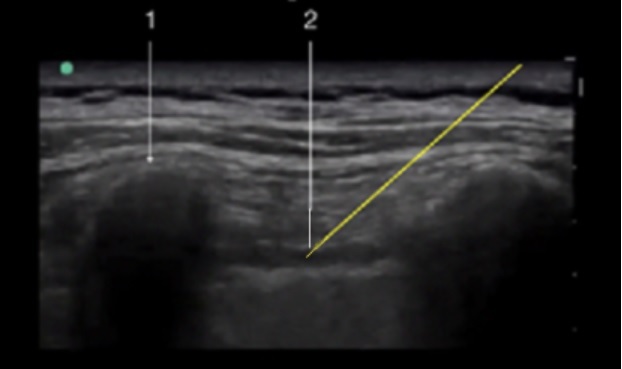

Paravertebral Parasagittal Approach Image

1. Transverse Process

2. Internal Intercostal Membrane

Yellow Arrow – Needle Approach